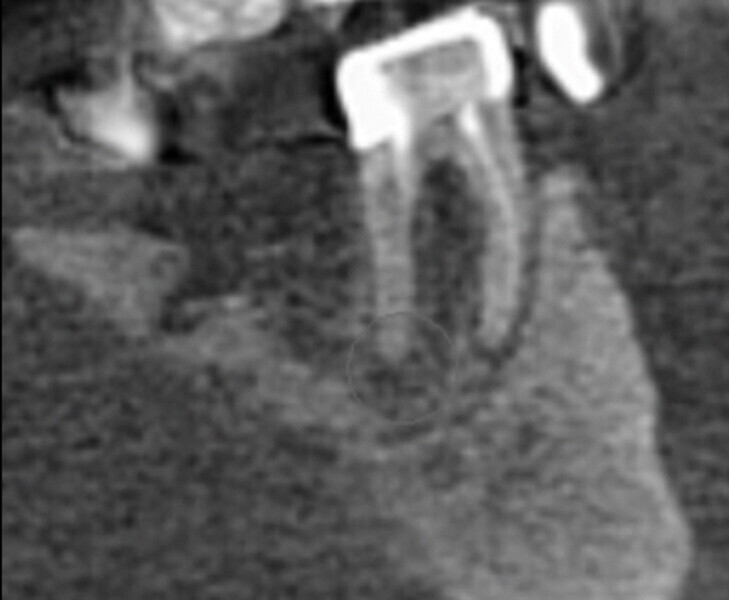

In this first case, the patient, who lived abroad and was unable to travel at the time, had swelling of her right mandible (Fig. 6), had had breast cancer and had been under bisphosphonate treatment for 18 months. She sent a panoramic radiograph (Fig. 7), and this showed a minor apical infection of the mandibular right first molar, which had undergone endodontic treatment. A CBCT scan was then taken, and from examining her scan, we could clearly see an area of bone densification (Fig. 8). This should be a red flag because this indicates the start of bone necrosis.

7: Panoramic radiograph showing a minor apical infection of the mandibular right first molar and endodontic treatment.

Fig. 8: Axial view of the CBCT scan showing a small apical infection of the mandibular right first molar, surrounded by an area of dense ossification extending over a large part of her mandible.